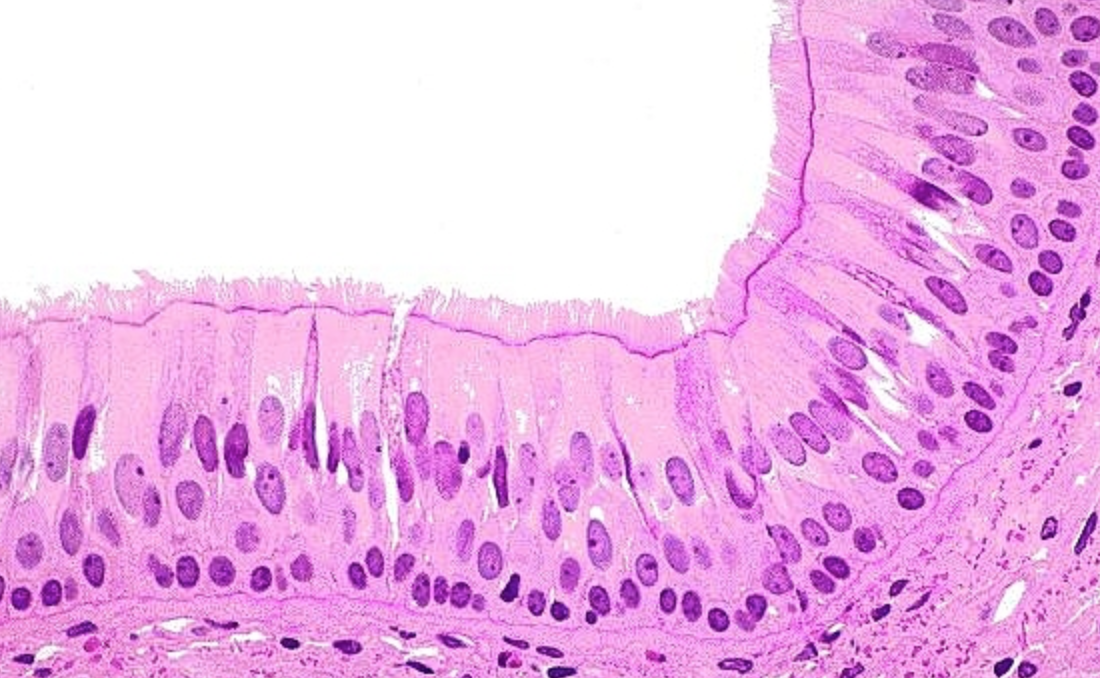

Pseuodostratified Ciliated Columnar Epithelium

single layer that looks like multiple layers that is taller than it is wide and has cilia on the top